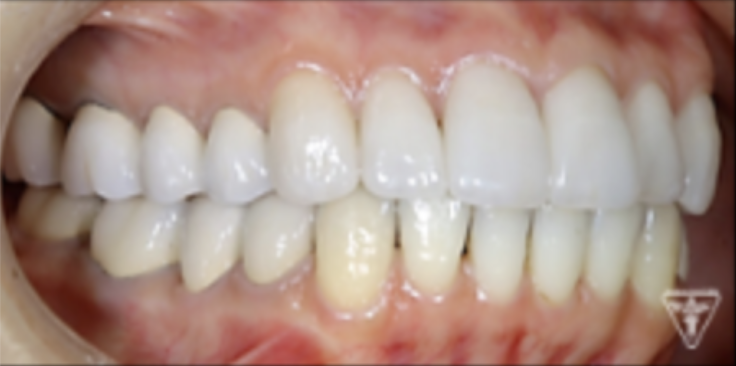

最終補綴物装着時

治療後